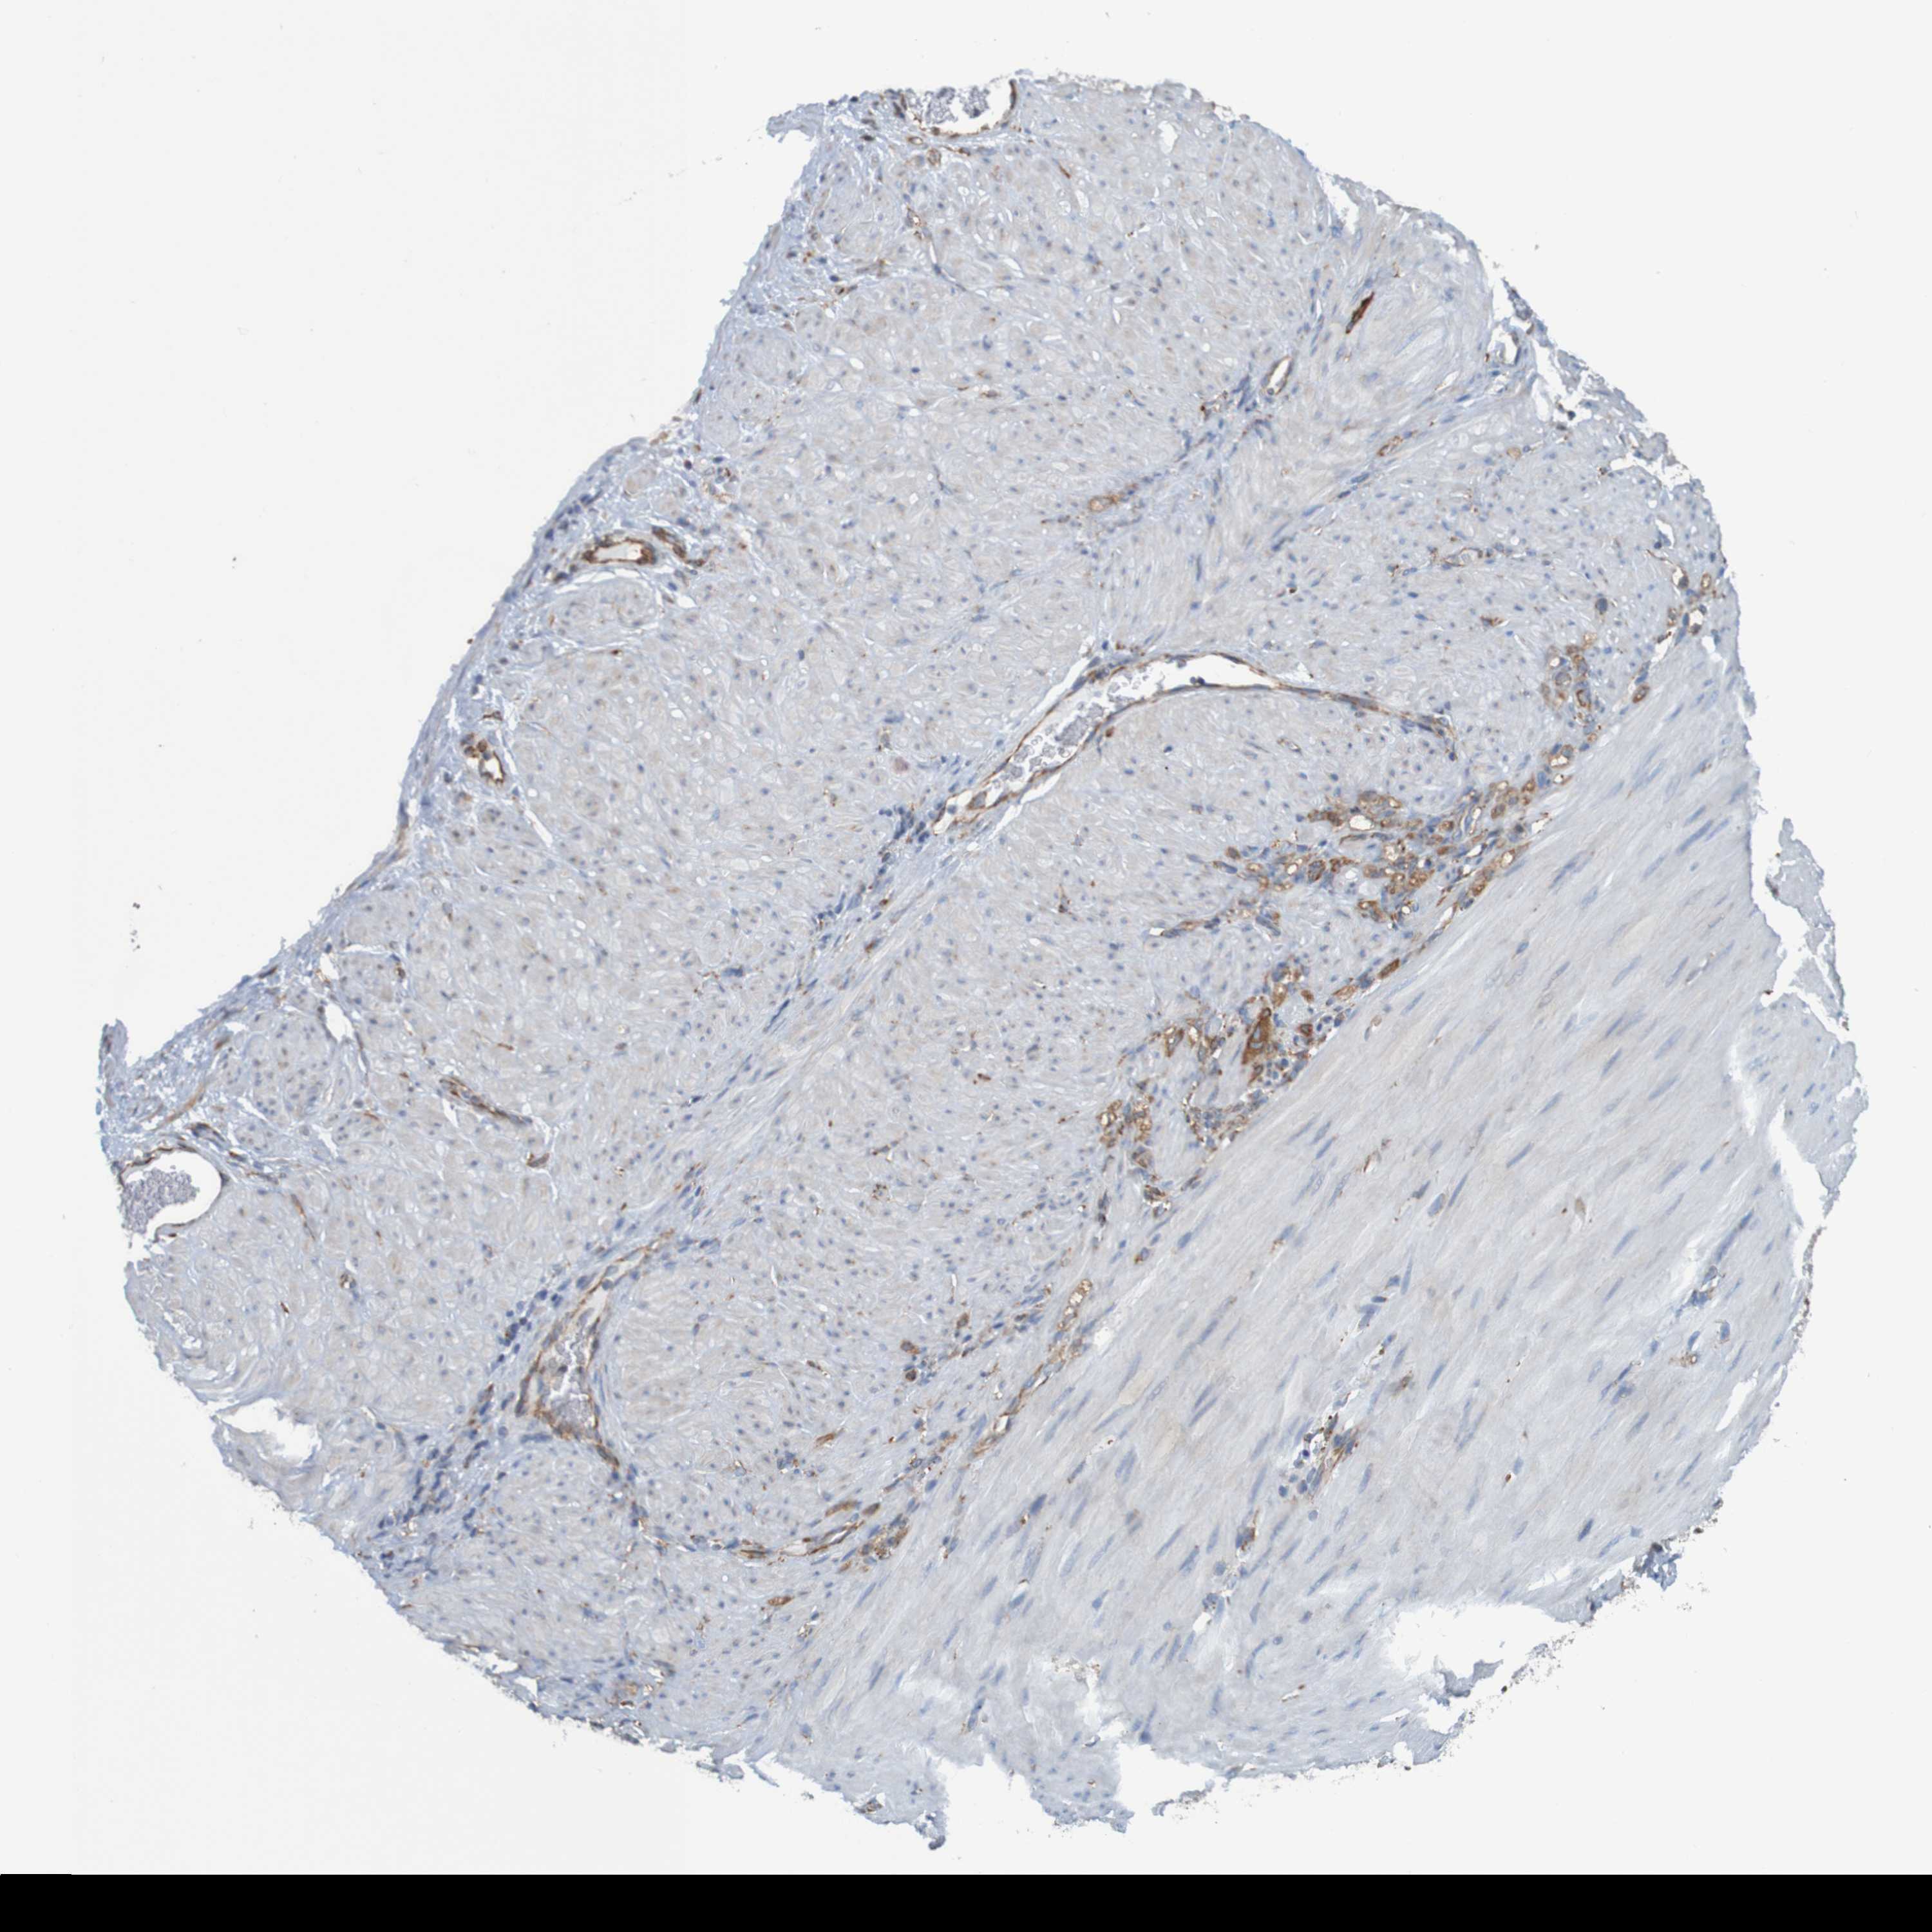

STOMACH CANCER - Protein expressioni

A mouse-over function shows sample information and annotation data. Click on an image to view it in a full screen mode. Samples can be filtered based on level of antibody staining by selecting one or several of the following categories: high, medium, low and not detected. The assay and annotation is described here.

Note that samples used for immunohistochemistry by the Human Protein Atlas do not correspond to samples in the TCGA dataset.

Antibody stainingi

Antibody staining in the annotated cell types in the current human tissue is reported as not detected, low, medium, or high, based on conventional immunohistochemistry profiling in selected tissues. This score is based on the combination of the staining intensity and fraction of stained cells.

Each image is clickable and will lead to virtual microscopy that enables deeper exploration of all samples and also displays staining intensity scores, fraction scores and subcellular localization as well as patient and tissue information for each sample.

Antibody HPA011276

Antibody HPA017062

Staining

High

Medium

Low

Not detected

Intensity

Strong

Moderate

Weak

Negative

Quantity

>75%

75%-25%

<25%

None

Location

Nuclear

Cytoplasmic/membranous

Cytoplasmic/membranous,nuclear

Adenocarcinoma, NOS

Adenocarcinoma, High grade